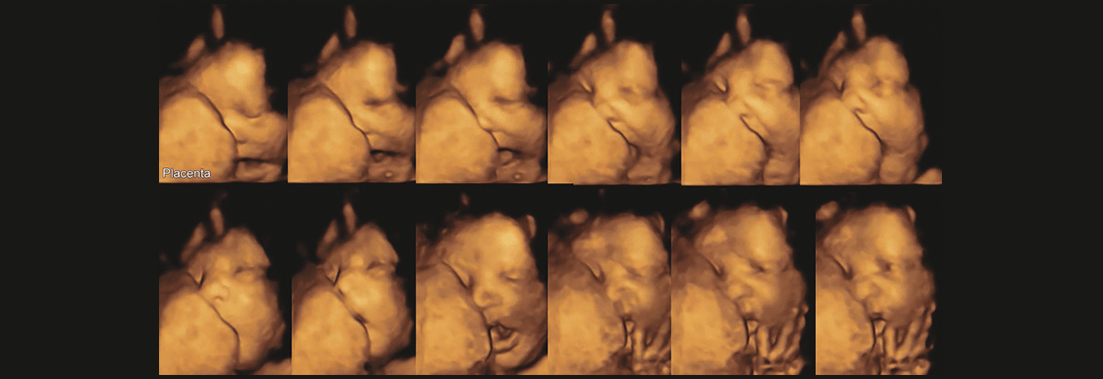

En, uzunluk ve derinlik boyutlarını içeren 3 boyutlu görünümün eş zamanlı olarak bir monitorde görüntülenmesine olanak sağlayan en son teknolojik ürünlerdir. Yüksek görüntü kalitesi ile dört boyutlu ultrasonda bebeğinizin tüm uzuvları ve hareketleri oldukça net ve hızlı bir şekilde izlenebilmektedir. Önceden üç boyutlu ultrason cihazlarıyla yapılan incelemeler ile anne rahmindeki bebeklerin hareketleri gecikmeli olarak görüntülenebilirken, 4 boyutlu ultrasonografi ile bebeğin kaşlarını çatması, gülmesi, esnemesi, parmak emmesi gibi hareketleri anlık ve hızlı bir şekilde izlenebilmektedir. 4 boyutlu ultrason, anne karnındaki fetüsün ayrıntılı sakatlık taramasında çok etkindir ve aşağıda belirtilen konularda tanı ve teşhis konusunda önemli bir yere sahiptir: